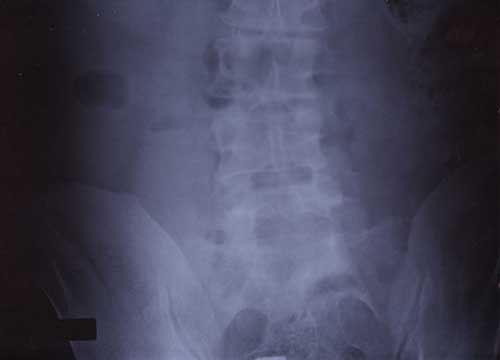

21st January 2000